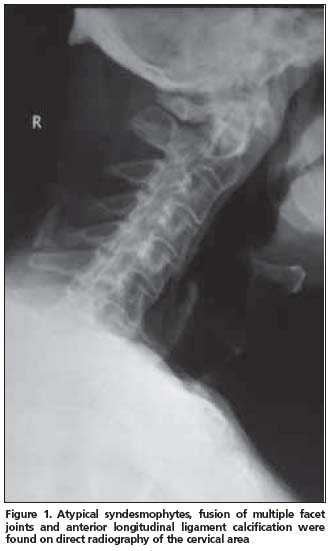

Anterior longitudinal ligament calcification, fusion of multiple facet joints and atypical syndesmophytes were found on cervical spine X-rays (Figure 1) and coarse, asymmetrical syndesmophytes were seen on thoracic (Figure 2) and lumbar spine (Figure 3) X-rays. No abnormalities suggesting PsA or gout were seen on hand and foot radiographs. The magnetic resonance imaging (MRI) of the sacroiliac joint and computerized tomography (CT) of atlanto-axial joint were normal.

PsSpA is observed in 5% of the PsA patients and may be clinically confused with AS[12]. The clinical characteristics of our case also resembled AS. An inflammatory type of low back pain was present and chest expansion was 2 cm. X-rays revealed a predominance of axial involvement. However, a normal sacroiliac joint MRI and lack of a typical syndesmophyte appearance made the AS diagnosis unlikely.